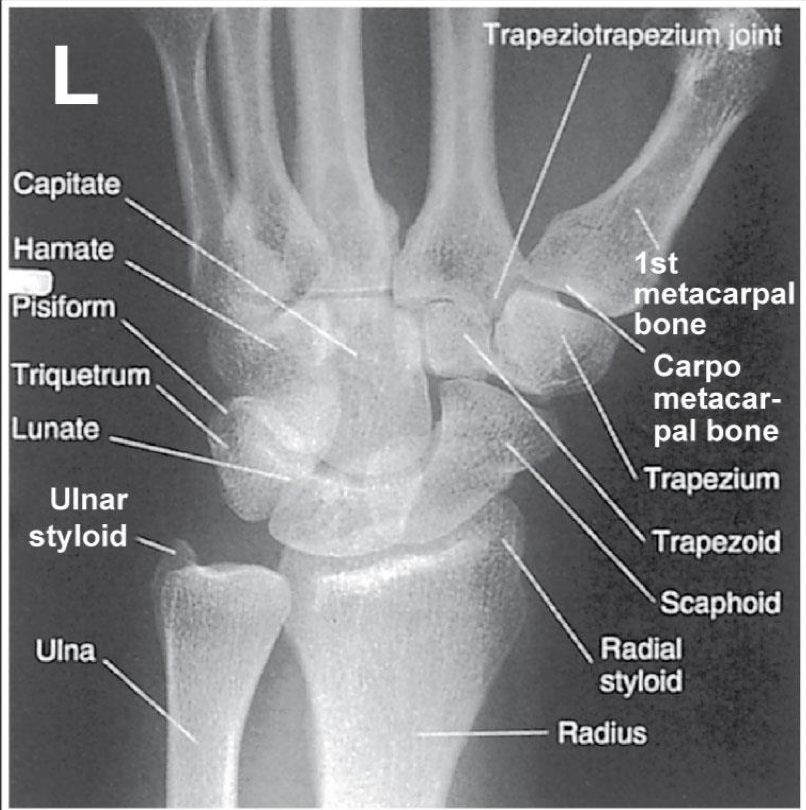

PA 45 degree Oblique Wrist

Patient Position

Same as PA Wrist

Part Position

Hand is pronated and wrist is rotated 45 o laterally

Thumb side “up”

Hand should be arched slightly

Long axis of 3rd metacarpal in line with long axis of forearm

CR

Centered to mid-carpal region

Collimation

Evaluation Criteria for PA 45 degree Oblique

• Distal radius, ulna, and carpals demonstrated

• Radius & ulna partially superimposed

slight overlap of metacarpals

• Center of field at midcarpals

• Trapezium and trapezoid seen in its entirety

• Scaphoid is minimally superimposed by trapezoid & capitate

• Exposure factors: soft tissue + bony detail

3rd metacarpal lines up with middle of wrist